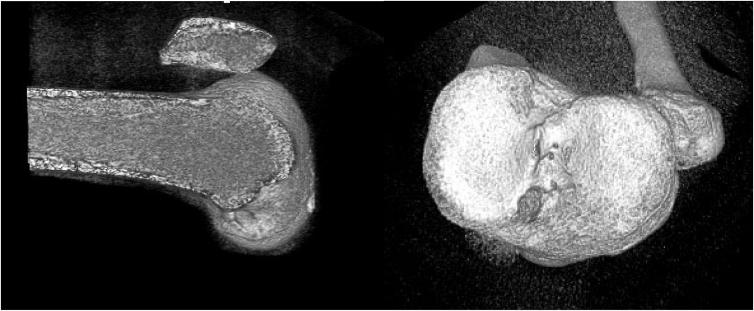

使用股四头肌腱经圆形矩形骨隧道进行解剖学前交叉韧带重建的技术

Technique of Anatomical Anterior Cruciate Ligament Reconstruction With Rounded Rectangular Bone Tunnels Using the Quadriceps Tendon.

The technique presented not only aligns with the current trend of using the quadriceps tendon in anterior cruciate ligament (ACL) reconstructions but also introduces rounded rectangular bone tunnels, which better mimic the native ACL's morphology. This ACL reconstruction improves footprint coverage using rounded rectangular bone tunnels in the femur and tibia. This method could significantly influence clinical practices, particularly in treating younger patients with ACL injuries.

所提出的技术不仅符合当前在前交叉韧带(ACL)重建中使用股四头肌肌腱的趋势,而且还引入了圆形矩形骨隧道,其更能模拟天然ACL的形态。这种ACL重建通过在股骨和胫骨中使用圆形矩形骨隧道来改善足迹覆盖。这种方法可能会显著影响临床实践,特别是在治疗年轻的ACL损伤患者时。